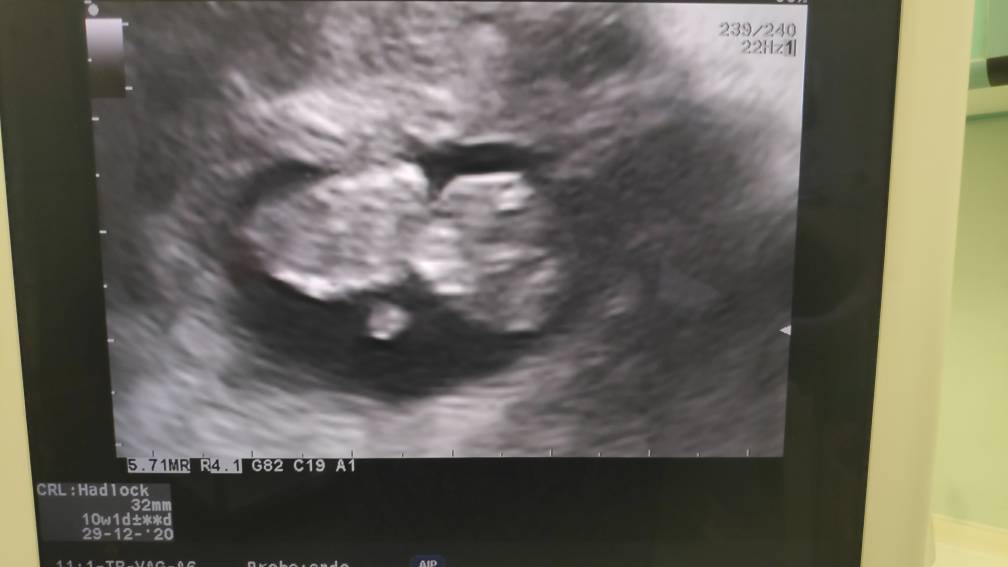

Jestem po wizycie [emoji3059]

Serduszko bije, ludź urósł [emoji3590]

Tylko tętno troszkę zbyt szybkie (175) ale podobno to się zdarza w pierwszym trymestrze więc mam się nie denerwować [emoji846]

A oto całe 3,2 cm człowieka [emoji3590]